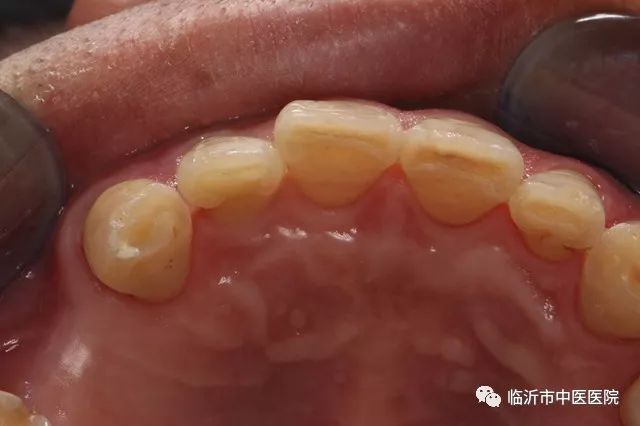

如果门牙牙折断面积较大,牙髓暴露,但根部完好,牙齿不松动,应首先在局麻下进行牙髓治疗即根管治疗,治疗后,在牙断面打两根螺纹钉,然后将断端复位,再取下备用。断面经粘接前的处理,涂粘接剂,用树脂充填牙髓腔,将断面对准粘接,光照固化。亦可在断面粘接后,将牙表面磨去一薄层,用贴面材料覆盖,修整外形,磨光,这时患牙的外形颜色与邻牙协调。